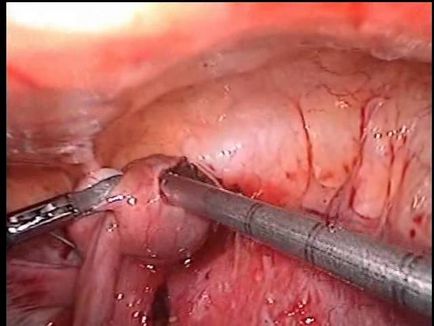

Van egy másik módszer a korai diagnózis - laparoszkópia. Ez az eljárás csak akkor, ha feltétlenül szükséges, ha egy nő tartalmazza azokat az alapvető patológiai a tüneteket. Segítségével egy laparoszkópot ellátott miniatűr kamera, az orvos meg tudja állapítani a helyét az embrió, és hogy erősítse meg vagy cáfolja a diagnózist. Gyakran előfordul, hogy az alak a méh terhesség fordul elő, rendellenességek és nyilvánvaló hasonló tüneteket, mint méhen kívüli. Ha a diagnózist, a megtermékenyített petesejt azonnal eltávolítjuk. Ezzel elkerülhető a törés a cső, ami előfordulhat 6-10 hetes terhesség.

Méhen kívüli terhesség. laparoszkópia